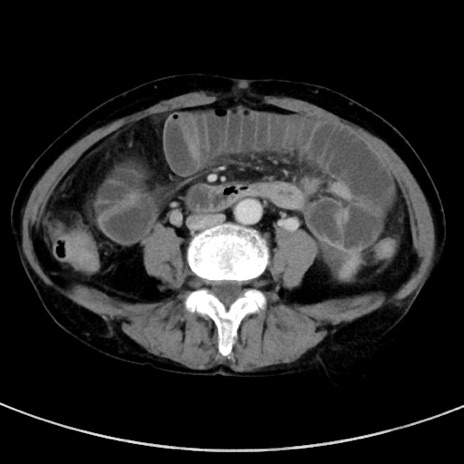

症例23(横断像)

【症例】70歳代女性

【主訴】下腹部痛・嘔吐

【現病歴】2日前より腹痛あり。昨日嘔吐あり。症状改善しないため来院。

【既往歴】胃GISTに対して胃部分切除後。

【身体所見】BT 37.1℃、BP 128/77mmHg、腹部:平坦・軟、下腹部に圧痛あり。

【データ】WBC 10200、CRP 0.31